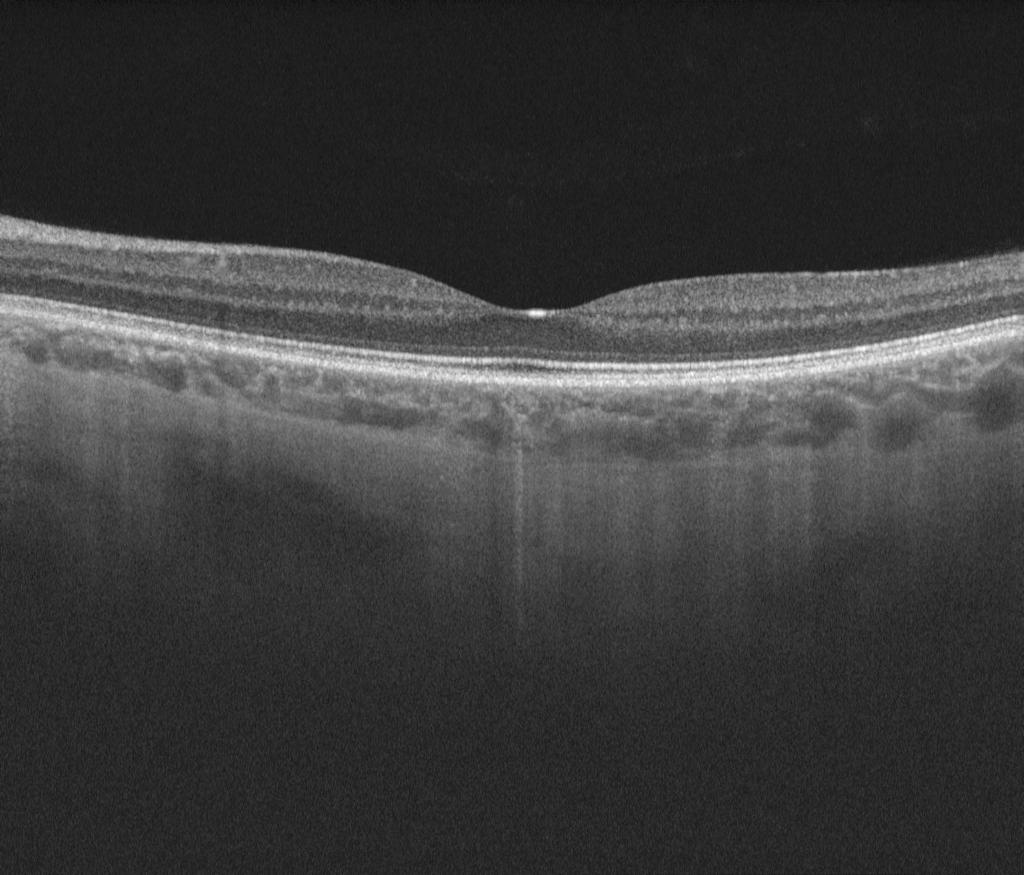

Many high street optometrists and opticians now use retinal scans (OCT machines)

to check the health of the back of your eye (some example images are shown below). Mr Jonathan Park specialises in the review and management of these retinal scans.